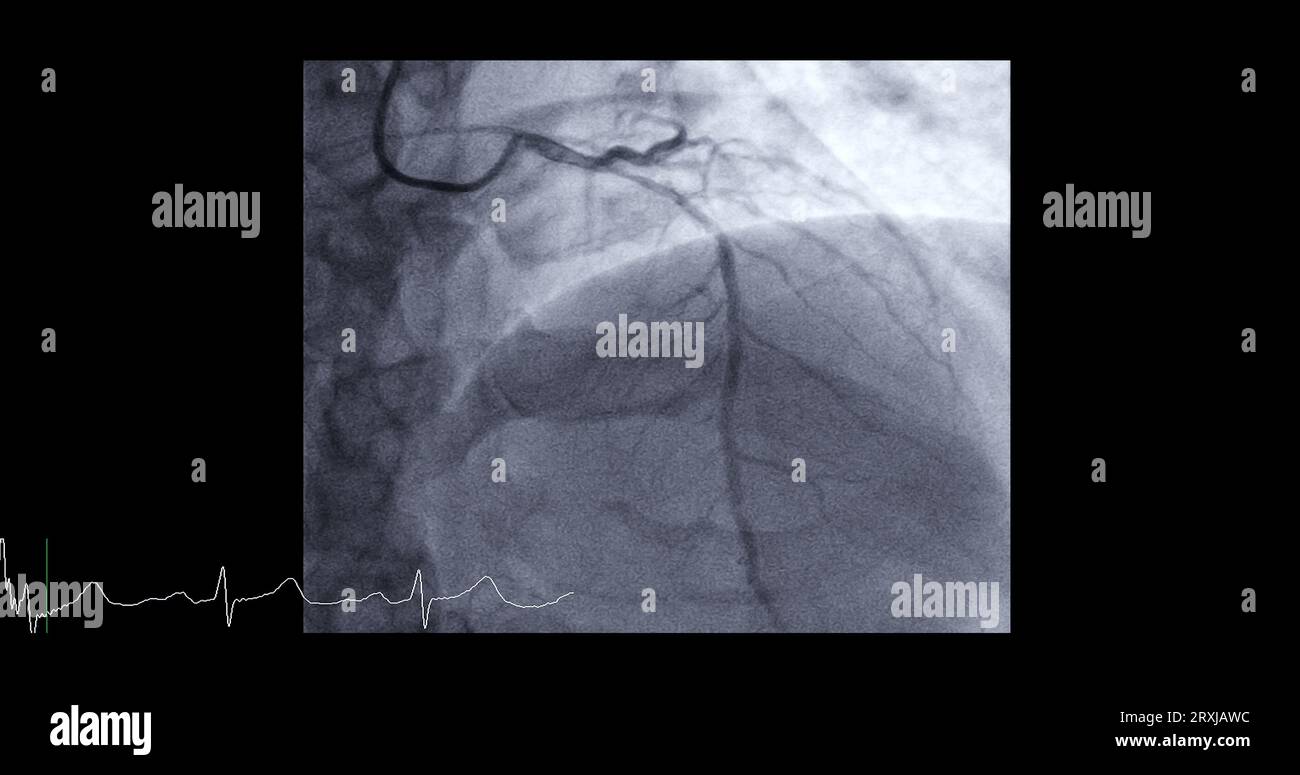

Cardiac Catheterization On Left Anterior Descending Artery Can Help What Does Cardiac Catheterization Diagnose Cardiac catheterization (also called cardiac cath, heart cath, or coronary angiogram) is a procedure that allows your doctor to see how. Cardiac catheterisation is an invasive diagnostic procedure that provides important information about the structure and function of the heart. The most frequent indications for right heart catheterization are to assess hemodynamics, diagnose pulmonary hypertension, guide therapy, and assess need. What Does Cardiac Catheterization Diagnose.

Cardiac catheterization on left anterior descending artery (LAD) can What Does Cardiac Catheterization Diagnose Cardiac catheterisation is an invasive diagnostic procedure that provides important information about the structure and function of the heart. Cardiac catheterization (also known as cardiac cath, heart cath, or coronary angiogram) is an imaging heart procedure that’s. The most frequent indications for right heart catheterization are to assess hemodynamics, diagnose pulmonary hypertension, guide therapy, and assess need for cardiac transplantation. What Does Cardiac Catheterization Diagnose.